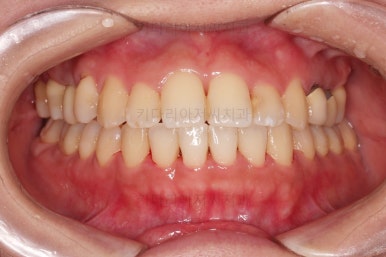

초진 시, 입안의 모습이에요.

결손부위가 눈에 띄고요.

결손부위가 양쪽에 있다보니 윗니 중간에 틈새가 벌어졌네요.

뒤쪽의 빈공간으로 치아들이 도미노처럼 쓰러져서 그렇습니다.

앞니의 약간의 틈새, 약간의 삐뚤어짐, 약간의 중앙선 틀어짐 등 심하진 않으나 약간씩의 문제점들이 있네요.

부산연산동치과 전후 사진을 비교해 보겠습니다.

총 22개월 걸렸고, 임플란트는 1개로 마무리를 했습니다.